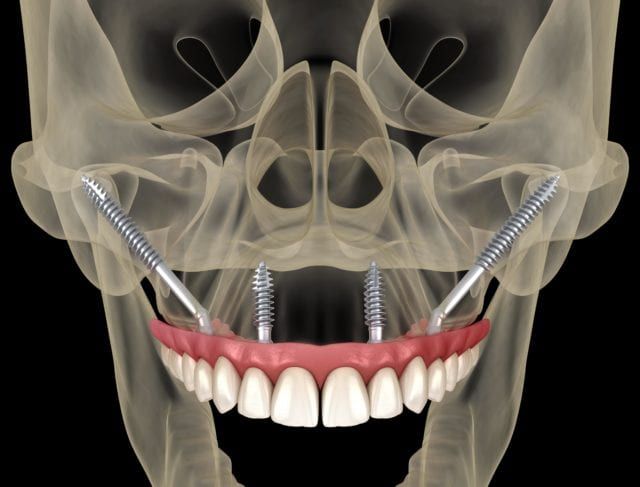

This advanced surgical technique requires a high level of skill and training. At Cherry Street Oral & Facial Surgery, our team is formally trained and experienced in zygomatic implant placement, ensuring safe and accurate results.

Our team is proud to offer zygomatic implants to individuals who have experienced significant bone loss in the upper jaw and need a dependable alternative to traditional implants. These implants have been used successfully for decades and are backed by long-term clinical success.